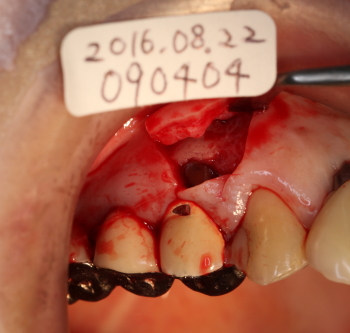

FOP(歯肉剥離掻爬術を行う

骨欠損部に骨補填剤を充填